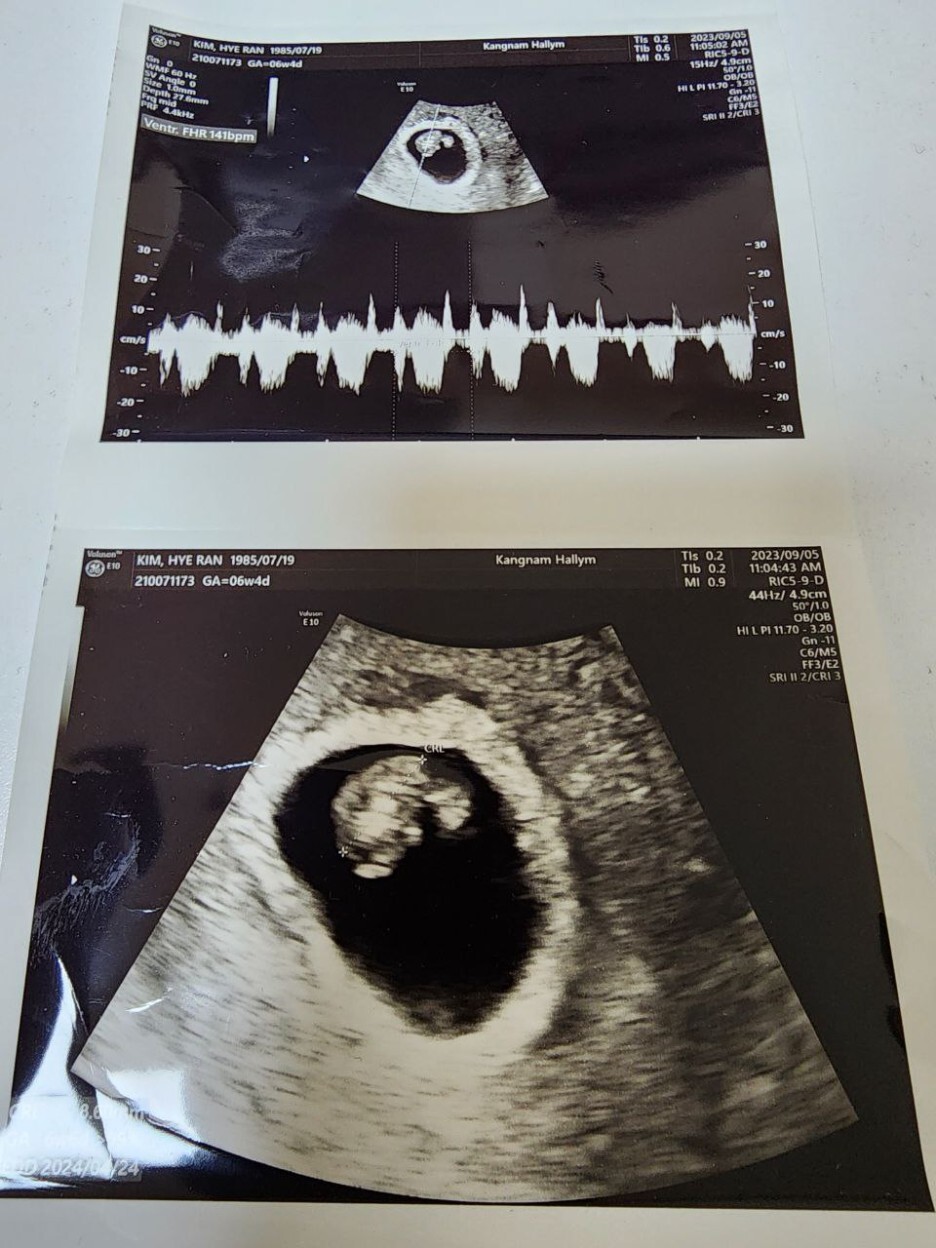

원래 초기에는 항상 그렇듯 병원을 자주 방문하게 된다. 보통 안정기에 접어드는 20주차 안에 유산되는 경우가 종종 있기 때문이다. 어차피 이 기간 안에 유산이 되는 경우는 내가 어찌할 수 없는 경우가 대부분이다. 게다가 태동을 전혀 느낄 수 없기 때문에 아기가 잘 있는지 아닌지 알기도 어려워 오로지 산부인과에 방문해서 초음파를 보는 방법 밖에는 불안한 마음을 달랠 길이 없다. 그런 이유에서 임신 초기에 산부인과를 자주 방문하게 된다. 의사 선생님도 그런 내 마음을 아시는지 또 오라고 하셔서 거의 5일 만에 다시 병원을 방문했다. 의사 선생님 말로는 아기집 크기도 좋고 위치도 좋다고 걱정할 부분이 전혀 없다고 하셨다.